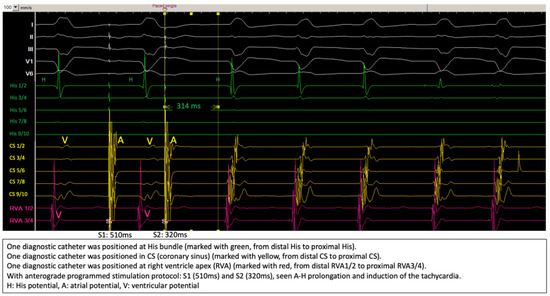

2. Method and Results

2.2. Diagnostic Workup